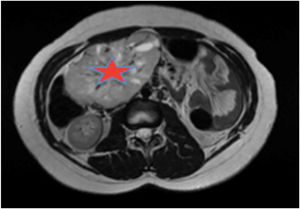

Se solicitó un estudio de localización mediante resonancia magnética nuclear (RMN) abdominal (figura 1 del anexo), que mostró una gran masa abdominal a nivel paraaórtico derecho compatible con un paraganglioma intraabdominal y estudio de extensión mediante tomografía computarizada (TC) toracoabdominal con contraste (figura 2 anexo) y gammagrafía con MIBG 131 (figura 3 anexo), que no mostraron lesiones a ningún otro nivel.